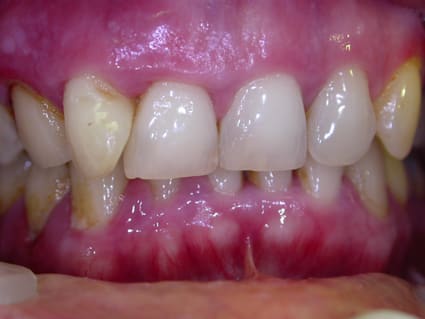

22/02/2007 à 00h31

tiens un cas typique .....paro de l'adulte active ......les premières seances prise en charge du patient et litho ......au bout de 3 mois pas de franche amélioration ....persistance d'une inflammation .....bien que la patiente soit efficace.......tests microbio .....reponse + pour PG sur 3 secteurs à des taux de 10 puissance 7 + du BF 10 puissance 6 + des treponèmes 10puissance 6 .......ordonnance de flagyl pendant 14 jours ......tout s'est alors arrangé très simplement .....j'ai fini mes litho ( j'ai retrouvé plein e tartre et de petits surfacages ponctuels ( ultrason satelec) et c'est tout ......lors du dernier contrôle de maintenance 2 ans après il y a de petits defauts de brossage en interdent mais c'est stable et le sondage est maxi à 3 mm partout......si j'avais d'emblée fait un curetage certes avec un bon contrôle de plaque j'aurais pu avoir une belle amelioration mais je pense pas totale et une recidive ensuite ....

au passage le fluorure d'etain tache .......